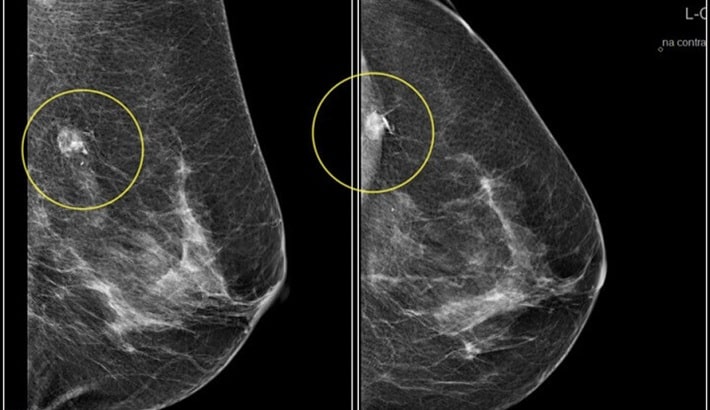

نقش دستگاه ماموگرافی در تشخیص دقیق

دستگاه ماموگرافی وظیفه دارد کوچکترین تغییرات در بافت سینه را آشکار کند. اگر دستگاه از وضوح کافی برخوردار نباشد؛ ممکن است ضایعات کوچک یا میکروکلسیفیکاسیونها (ذرات ریز کلسیم که اولین نشانههای سرطان پستان هستند) دیده نشوند. این موضوع میتواند تشخیص را به تعویق بیندازد و روند درمان را سختتر کند. بنابراین کیفیت دستگاه مستقیماً با نجات جان بیمار ارتباط دارد.

در گذشته ماموگرافیها با سیستم آنالوگ انجام میشدند که تصاویر کیفیت پایینتری داشتند. اما امروز ماموگرافی دیجیتال امکان بررسی جزئیترین بخشهای سینه را با وضوح بسیار بالا فراهم کرده است. در یک مرکز ماموگرافی که از تجهیزات دیجیتال استفاده میکند، احتمال تشخیص زودهنگام بیماری چند برابر بیشتر است. مرکز تصویربرداری تابا نیز با بهرهگیری از همین تکنولوژی بهروز، توانسته دقت تشخیص را به حد چشمگیری افزایش دهد.